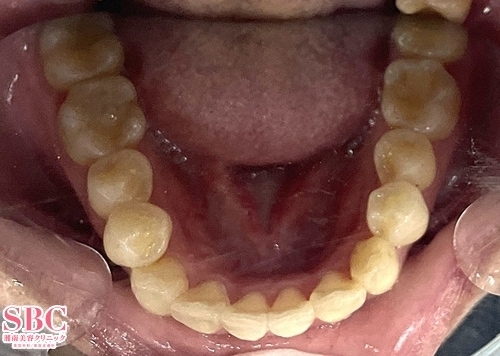

施術前

施術後12ヶ月後

インビザラインGOで治療されたお客様です。12か月の矯正で改善しています。※お客様の着用日数により、完成時期が前後します。マウスピース矯正は医師の設計とお客様が装着時間をお守りいただくことで良い結果が得られます。お客様、マウスピース矯正お疲れ様でした^^

インビザラインGOで治療されたお客様です。

12か月の矯正で改善しています。

※お客様の着用日数により、完成時期が前後します。

マウスピース矯正は医師の設計とお客様が装着時間をお守りいただくことで

良い結果が得られます。

お客様、マウスピース矯正お疲れ様でした^^